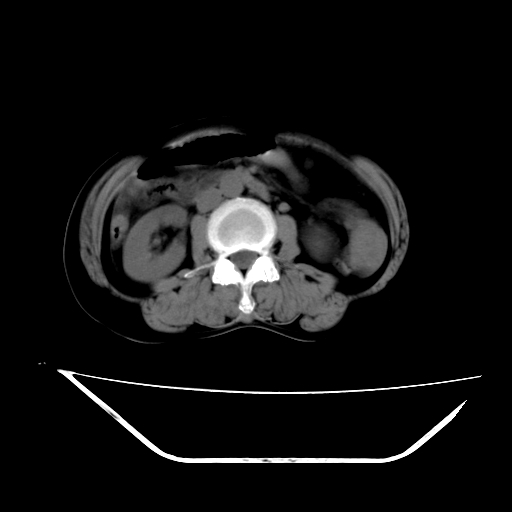

2008-11-10ct平扫(其间去中山医院诊治未行特殊治疗)

2008-11-10ct平扫见并肝内、血膜下血肿基本吸收,肝内低密度灶缩小。此时再做增强ct应有显着意义。对患者/医者都好!

患者自6月至11月,如果是肝癌,没有经过特殊治疗,想必应该会有所进展吧,而不是ct所见,反而似有病灶减小的趋势。建议增强。